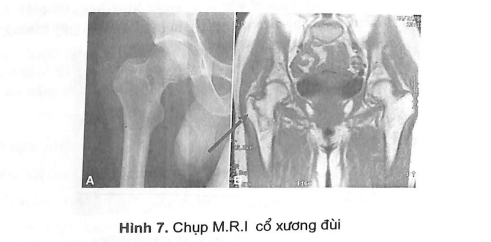

3.9.3. Một số phương pháp chụp hệ xương khớp đặc biệt

- Chụp cắt lớp vi tính: C.T Scanner (để chẩn đoán các loại u xương, gãy cổ xương đùi...)

- Chụp cộng hưởng từ: M.R.I (trong chấn thương cột sống, cổ xương đùi...).